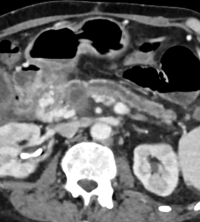

This program aims to provide advanced subspecialty training in hepatobiliary and gastrointestinal imaging at an expert level.

- Deliver expert-level subspecialty training in hepatobiliary and gastrointestinal imaging, with a strong focus on multimodality approaches and complex abdominal pathologies, in line with current international standards

- Strengthen advanced diagnostic imaging expertise through comprehensive, case-based and evidence-based knowledge